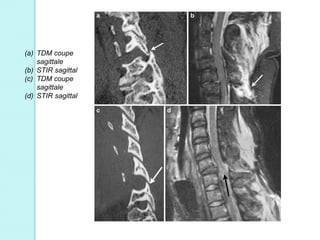

(a) TDM coupe

sagittale

(b) STIR sagittal

(c) TDM coupe

(d) STIR sagittal

2. Lésions enflexion-rotation – Importante hyperflexion associée à un rotation Souvent instables – TDM : Subluxation des facettes articulaires – +/- fractures des facettes ou des corps vertébraux Car atteinte des complexes ligamentaires, des disques ou des capsules articulaires

• 42.

TDM : Subluxation rotatoired’une facette articulaire  Coupe axiale : Signe caractéristique de la « facette dénudée »  +/- fracture associée  Reconstructions sagittales: Facettes articulaires « sautées » ou « perchées » Uni ou bilatérales